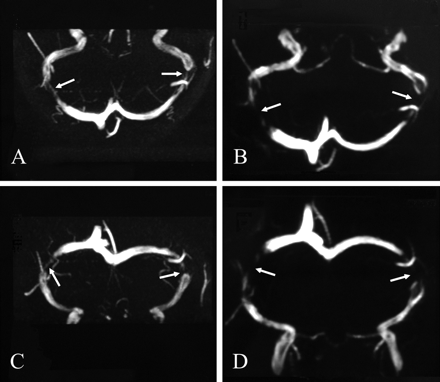

14个病人的特点,研究了在演示和随访总结表1和2。在基线评估,只有症状的持续时间,频率的视觉症状,患者脑脊液压力值的不同,没有视神经乳头水肿。基线脑MRV显示双边狭窄的midlateral部分TSs在所有患者(图)。双边TS狭窄坚持所有的患者在随访期间。在过去的几年里,在医疗、9(64%)的14颅内高压症患者无症状。在这些患者中,连续脑脊液压力测量记录压力值的归一化(平均H = 140.11毫米2O, SD H = 33.26毫米2O),没有观察到任何变化的外观TSs MRV(见图)。在这组患者脑脊液压力,正常化的衰减指数也记录(体重指数= 31.4,SD = 4.69)。其余情况下引起颅内压症状和体征,双边TS狭窄坚持MRV,腰椎脑脊液压力仍然高企在随访期间(H = 259.8毫米2O, SD H = 34.34毫米2O)、体重指数(= 34.14,SD = 4.08)并没有显示任何变化对基线值。后续的持续时间为6.8年(平均6.2年,范围3 - 6.8年)。